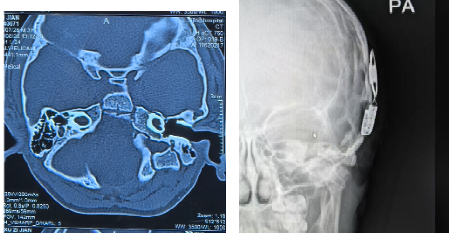

患儿为先天性聋哑儿童,术前评估为双耳极重度感音神经性聋、双侧耳蜗前庭共腔畸形合并中耳发育畸形,手术难度与风险较大。术前,刘晖主任医师、许珉主任医师及其团队全面评估患儿听力学、影像学及发育状况,与家属充分沟通,并针对术中难点、并发症预防及术后康复等进行多轮研讨与周密准备。

术中,刘晖主任医师在变异解剖结构中精准定位面神经及圆窗龛,顺利植入电极,术中测试提示电极电阻正常,遥测反应良好。患儿在医护人员的悉心照料下,生命体征平稳。术后3天复查,显示电极位置良好,术后1周顺利出院。